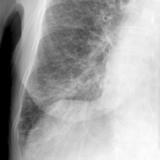

APE 3

Date: 11/05/2005

Views: 4001